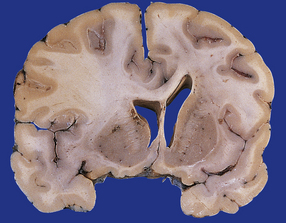

图示:少突胶质细胞瘤,这种浸润性肿瘤使额叶中的回旋和深部白质扩张,使纹状体和侧脑室变形,并导致扣带回的次f性突出。